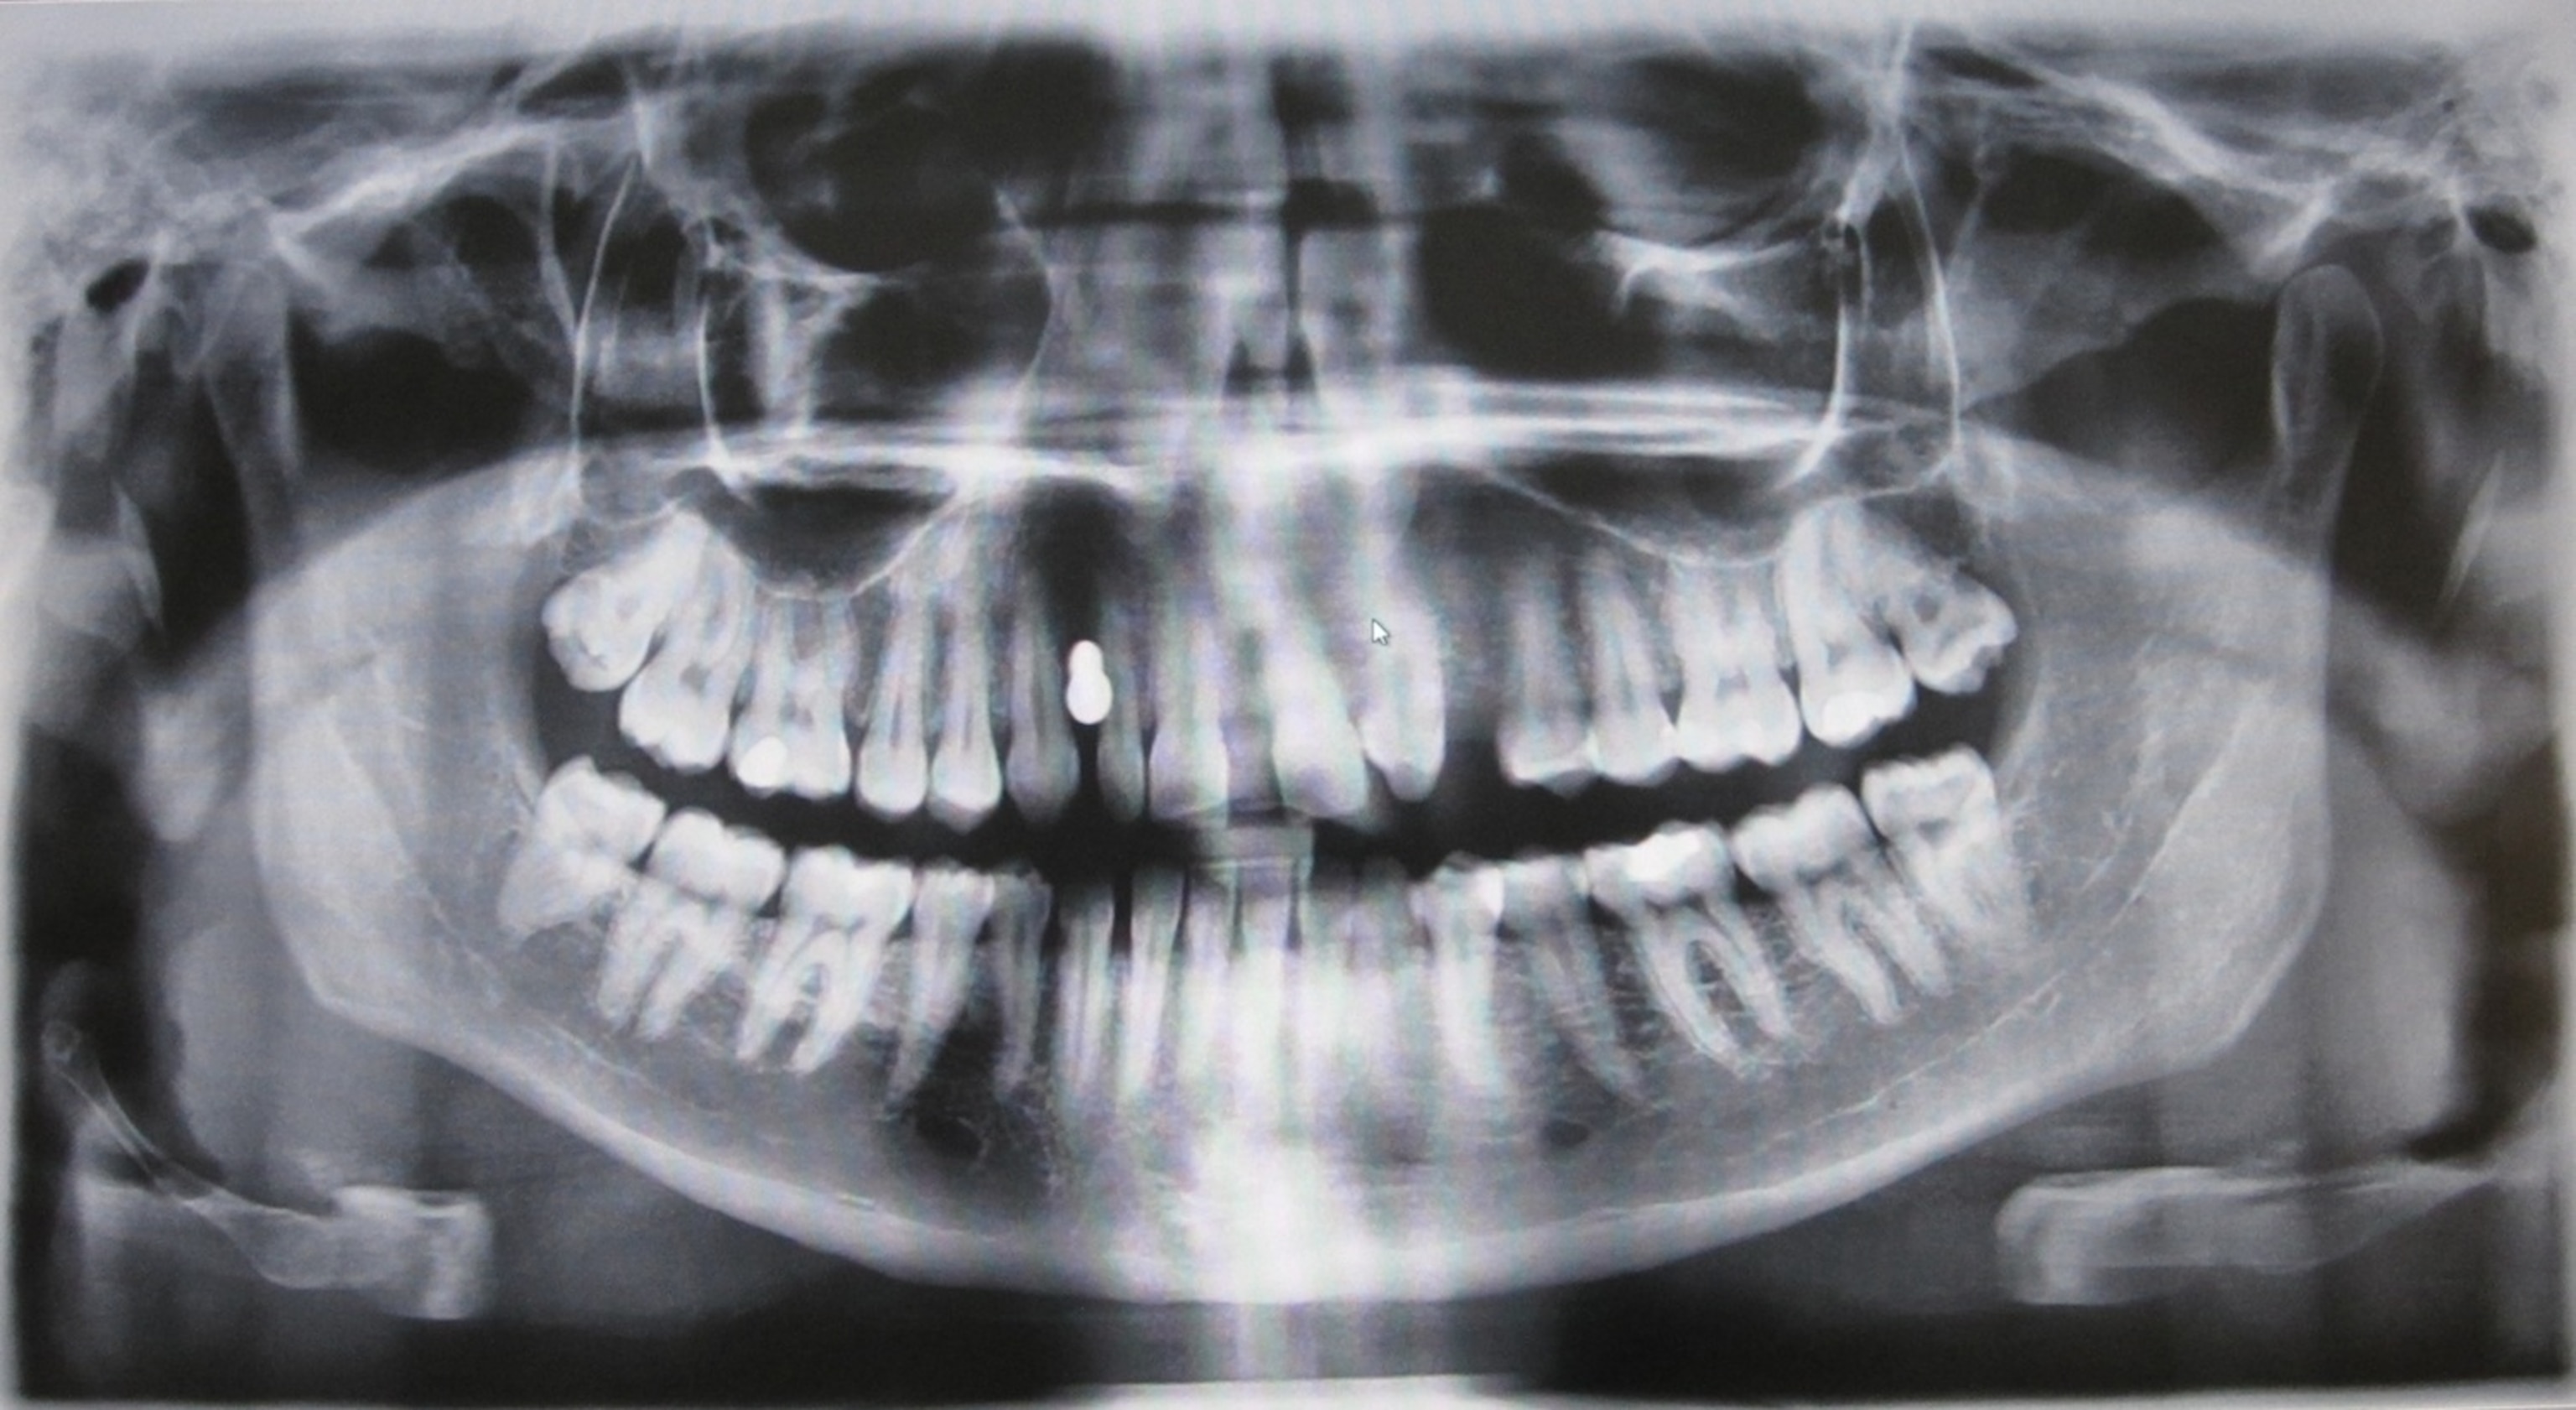

The human mouth is home to hundreds of species of bacteria. While some of them keep our mouths healthy, others can cause us trouble. One of the worst offenders is Streptococcus mutans. It lives in the nooks of our teeth, feeding on carbohydrates. It excretes lactic acid as waste, and the acid eats away at the enamel on which it rests. Over time, Streptococcus mutans can dig a hole in a tooth–otherwise known as a cavity.

These adaptations have made Streptococcus mutans spectacularly successful, and they’ve also provided us with a lot of misery. The cavities would be bad enough. Archaeological evidence indicates that cavities went from rare to common with the advent of agriculture. Making matters, worse, however, is the fact that when Streptococcus mutans gets into the bloodstream through the gums, it can make its way to the heart and cause problems there, too.